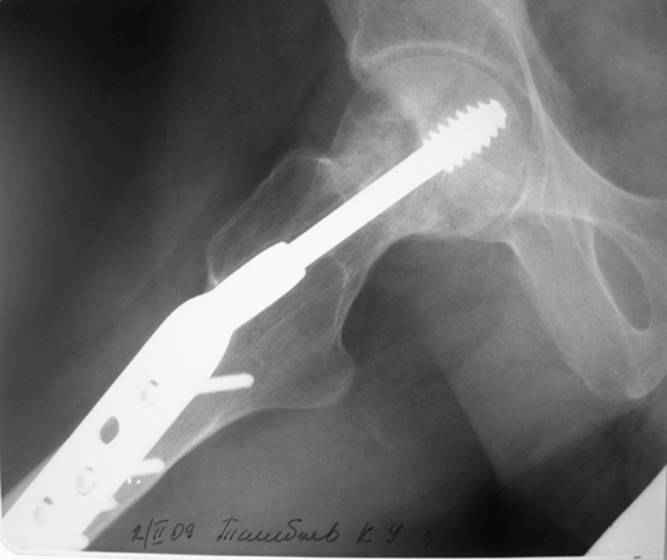

Больной Т. 1966 г.р.Травма 28.06.2007. Прооперирован в г. Бишкек, Оп: Остеосинтез правого бедра системой DHS. В последующем беспокоили периодические боли в правом тазобедренном суставе с иррадиацией в коленный сустав в область передней поверхности правого бедра. Лечился амбулаторно с незначительным эффектом. В 07.04.2008 по 08.05.2008 года лечился в госпитале ГУВД и СО в стационаре с Срастающийся перелом шейки правого бедра в условиях фиксации системой DHS – боли уменьшились.Боли обострились 03.02.2009 внезапно, госпитализирован. Результат - Псевдоартроз шейки правого бедра (имеются косвенные признаки разрушения спонгиозной части головки бедра)Планируется - Работает милиционером. Имеющийся опыт протезирования у данной категории во всех случаях в ближайшее время заканчивался дисквалификацией. Работоспособный возраст (43 года).Наиболее приемлемым и реальным методом лечения предполагается: Удаление конструкций из бедра. Заполнение полости от винта монолитным аутотрансплантатом из крыла (крылев) подвздошной кости. Медиализация большого вертела. Предполагаемый период нетрудоспособности 3-4 мес.

На более раннем снимке репозиция была, мягко говоря, далека от идеальной. Плюс перелом шейки слишком проксимальный для фиксации одном винтом. Неудача тут закономерный исход.

Но в данном случае DHS сыграл как имплант с угловой стабильностью, что привело к прорезыванию импланта в верхнем сегменте головки. Отсутствие трехточечной опоры и длинный имплант увеличивают нестабильность в шейке.

Если на рентгенограмме произошли изменения положения импланта более чем на 5 градусов от первоначального, миграция шурупов более чем 15 мм от кортекса, также потеря репозиции на 10 мм - это свидетельство несостоятельности импланта. Компьютерная томография уточнит все сомнения. В таких случаях бесполезно ожидать, что перелом срастется, лучше своевременно сообщить больному и принимать решительные меры по реконструкции.